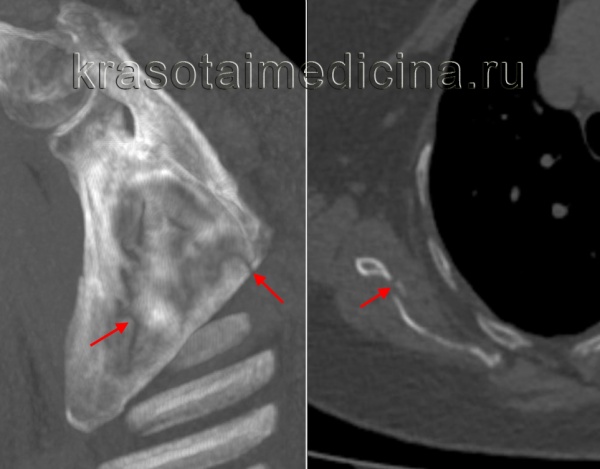

КТ ГОП. Патологический перелом 6 и 7 грудных позвонков (красная стрелка) на фоне вторичного поражения позвонков (синяя стрелка).